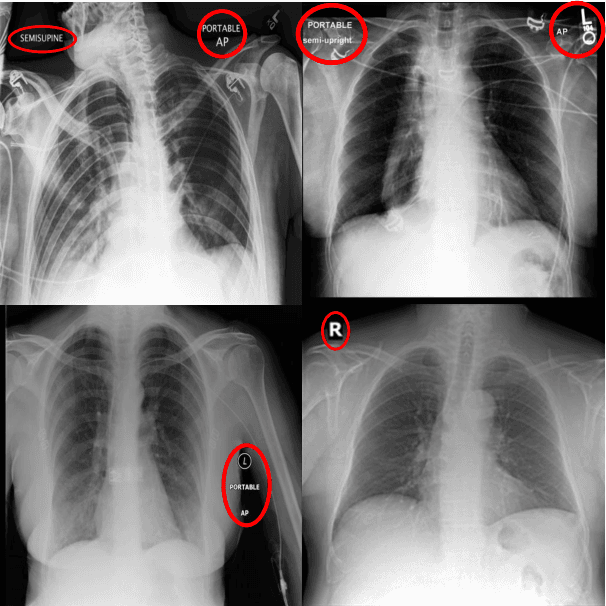

Abstract:Recent work has revisited the infamous task Name that dataset and established that in non-medical datasets, there is an underlying bias and achieved high Accuracies on the dataset origin task. In this work, we revisit the same task applied to popular open-source chest X-ray datasets. Medical images are naturally more difficult to release for open-source due to their sensitive nature, which has led to certain open-source datasets being extremely popular for research purposes. By performing the same task, we wish to explore whether dataset bias also exists in these datasets. % We deliberately try to increase the difficulty of the task by dataset transformations. We apply simple transformations of the datasets to try to identify bias. Given the importance of AI applications in medical imaging, it's vital to establish whether modern methods are taking shortcuts or are focused on the relevant pathology. We implement a range of different network architectures on the datasets: NIH, CheXpert, MIMIC-CXR and PadChest. We hope this work will encourage more explainable research being performed in medical imaging and the creation of more open-source datasets in the medical domain. The corresponding code will be released upon acceptance.